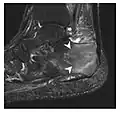

Figure 7: Fatigue fracture of the talus in a 25-year-old male basketball player with right hind foot and ankle pain, without history of trauma, and a normal initial radiograph (not shown). (a) One-month followup lateral radiograph shows normal appearance. (b) Sagittal T1-weighted MRI shows an irregular fracture line (arrow) within an ill-defined area of hypointensity corresponding to bone marrow edema.[1]

-

a -

b -

c

Figure 8: Proximal diaphyseal fatigue fracture of the tibia in a 20-year-old man with a history of regular jogging. (a) Lateral radiograph shows no obvious fracture lines but a subtle localized medial tibial cortex periosteal reaction (arrows). (b) Sagittal reformatted CT image acquired 1-month after the radiograph shows a linear hypoattenuation in the tibial cortex (arrowhead), as well as obvious periosteal thickening (arrows). (c) Sagittal T2-weighted fat-saturated image acquired the same day shows an area of hyperintensity spreading over the proximal tibia (arrows), which is consistent with the presence of proximal tibial fracture.[1]